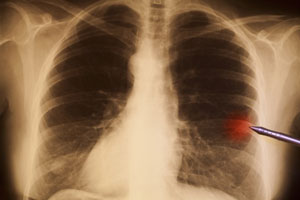

Kaszel jest złożonym objawem występującym w wielu chorobach układu oddechowego, przy czym u chorych na raka płuca może w istotnym stopniu ograniczać jakość życia. Na podstawie obserwacji u zwierząt rozpoczęto badania u ludzi mające na celu ocenę skuteczności leczenia kaszlu poprzez wpływ na czynność neurokinin.

Aprepitant jest lekiem zarejestrowanym do leczenia indukowanych chemioterapią nudności i wymiotów, a przedstawione badanie było pierwszym oceniającym jego przydatność jako leku przeciwkaszlowego. Aprepitant jest centralnie działającym antagonistą receptora neurokininy-1 (NK-1). Do przedstawionego, podwójnie zaślepionego, jednoramiennego badania klinicznego z kontrolą placebo włączono chorych na raka płuca z kaszlem o dużym nasileniu. Chorzy otrzymywali aprepitant w dawce 125 mg pierwszego dnia, a następnie 80 mg w drugim i trzecim dniu, albo odpowiadające dawki placebo. Po trzydniowej przerwie dokonywano zamiany grup terapeutycznych (dni 7-9). Przez 24 godziny przed podaniem leku aktywnego lub placebo oraz w trakcie badania chorzy nosili specjalne urządzenie rejestrujące liczbę epizodów kaszlu na godzinę. Urządzenie to noszone przez chorych w pasie przypominało saszetkę i zostało zarejestrowane przez FDA. Niewielki mikrofon przypięty do ubrania umożliwiał ambulatoryjne monitorowanie kaszlu. Chorzy wypełniali też odpowiednio zwalidowane kwestionariusze dotyczące nasilenia objawów oraz działań niepożądanych.